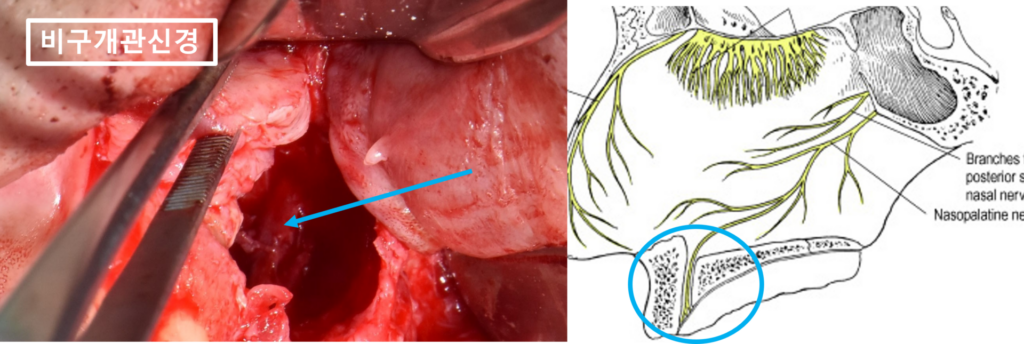

입천장 안쪽에는

비구개관신경이라고 해서

앞니의 입천장 부위의 감각을 담당하는

굵은 신경이 내려오는 통로가 있습니다.

치근단낭종이 점점 커지다가

(빨강색동그라미, 빨강색점선, 빨강색화살표)

비구개관신경이 통과하는 경로까지

침범해 있는 것이 관찰됩니다.

(검정색화살표, 노랑색점선)

포스팅 초반에

치근단낭종이 비구개관신경까지

닿아있다고 말씀을 드렸는데요,

24.05.24(치근낭적출술) – 43y 김OO님

거대 치근단낭종을 제거하면서

노출된 비구개관신경입니다.

(하늘색화살표, 동그라미)

물혹이 얼마나 커졌길래

입천장쪽 뼈까지 전부 흡수하면서

신경이 보일까요?